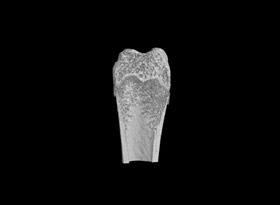

使用MicroCT可以詳細了解牙根管的三維形態(tài),測量根管的高度、體積、截面積、管壁厚度等。